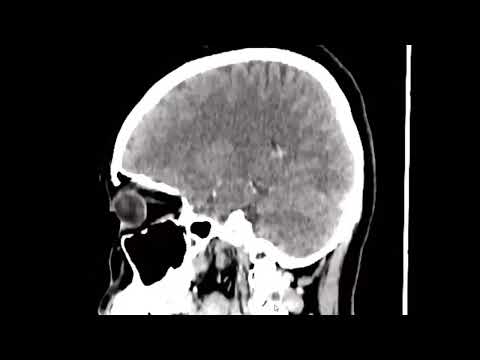

Hellow guys, Welcome to my website, and you are watching Middle cerebral artery bifurcation and M1 aneurysm clip reconstruction. and this vIdeo is uploaded by fornix00 at 2015-04-28T14:25:53-07:00. We are pramote this video only for entertainment and educational perpose only. So, I hop you like our website.